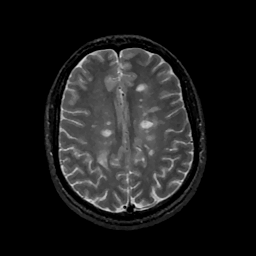

MR Study #11, May 5, 1991 -- Slice #34